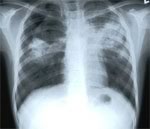

Целью Всемирного дня борьбы с туберкулезом является повышение осведомленности о глобальной эпидемии туберкулеза и усилиях по ее ликвидации. В настоящее время треть мирового населения инфицирована туберкулезом. В соответствии со статистическими данными Киевского городского центра здоровья, начиная с 1995 года, уровень заболеваемости активным туберкулезом в Украине неуклонно возрастал. В частности, в 2005 году количество заболевших увеличилось с 41,7 человека на 100 000 населения до 84,5 человек. Но уже начиная с 2006 года, темпы распространения туберкулеза замедлились. Снизилась и смертность от этой болезни.